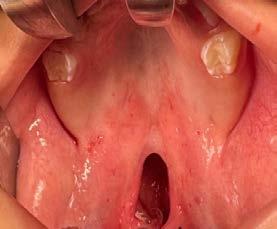

Introducción: La sinusitis odontogénica es una afección del seno maxilar ocasionada por el acceso de bacterias provenientes de los ápices de uno o más órganos dentales con proceso infeccioso activo, favoreciendo la inflamación de la mucosa, provocando una alteración en su producción y la presencia de otros síntomas. El tratamiento de primera elección es farmacológico y en caso de no presentar mejoría se realizará algún procedimiento quirúrgico según el estado en el que se encuentra el órgano dental comprometido y gravedad del padecimiento.

Materiales y métodos: Para este trabajo se realizó una investigación detallada de diversas fuentes de investigación como lo son pubmed, Science direct, entre otras y para el apartado del caso se decidió hacer un tratamiento mediante la comunicación oroantral Caso clínico: Paciente femenino de 49

años de edad, la cual es remitida por especialista en endodoncia por referir rinorrea, cefaleas y estornudos recurrentes con un año de evolución, ya tratada por otorrinolaringología sin mejoría.

Radiográficamente se observa lesión periapical con cercanía a seno maxilar por lo que se realiza extracciones de segundo y tercer molar superior derecho y limpieza a través de comunicación oroantral y cierre con la bola adiposa de Bichat.

Resultados y conclusiones: La bolsa adiposa de bichat para el cierre de comunicaciones intraorales es una excelente opción gracias a su vascularidad, volumen, versatilidad y capacidad de favorecer una metaplasia a tejido epitelial por su presencia de células madre.

En caso donde hay evidencia clara de una fuente de infección dental, nuestro tratamiento debe abordar primero la patología dental, desde un tratamiento de conductos, apicectomía o hasta la extracción dental. Si la endodoncia no tiene éxito o no es viable por distintos motivos, es aconsejable la extracción de dicho órgano dental. Durante la extracción de los dientes posteriores maxilares puede ocurrir una comunicación oroantral, esto se debe a la proximidad de las raíces al piso del seno maxilar.15,16

La literatura reporta diferentes técnicas para el manejo de la sinusitis maxilar y cierre de las comunicaciones oroantrales. Existen técnicas usando un colgajo bucal o mucoperióstico o un colgajo de rotación palatino el cual es preferible por localización, pero en comunicaciones más grandes la grasa bucal ha demostrado ser más adecuada.17

Caso clínico

Paciente femenino de 49 años de edad la cual acude a la consulta por odontalgia en segundo molar superior derecho, presenta obturación temporal y ausencia clínica de tercer molar superior

derecho (Figura 1). Especialista en endodoncia solicita cone beam en donde se visualiza lesión periapical extensa que involucra segundo y tercer molar ipsilateral y engrosamiento de la mucosa del seno maxilar sugerente de sinusitis maxilar crónica y su cercanía

con el tercer molar de dicha estructura (Figura 2).

Como antecedentes de importancia, la paciente refiere tratamiento previo por otorrinolaringología sin mejoría alguna, presentando rinorrea y obstrucción nasal constante ocasionando hiposmia, pero no correlacionándolo con una causa de origen dental.

Por lo que se propone procedimiento quirúrgico con la evidente comunicación oroantral al realizar las extracciones de los órganos dentales involucrados. Previa asepsia y antisepsia, colocación de campos estériles, extracción de segundo y tercer molar superior derecho e incisión envolvente con descarga mesial (Figura 3), rotación y afronte mediante puntos simples de la bola adiposa de Bichat para el cierre de la comunicación oroantral (Figura 4), farmacoterapia con base en amoxicilina con ácido clavulánico. Una semana después refiere no presentar rinorrea y mejoría al 100% de la obstrucción. Posterior a 6 meses de evolución clínica (Figura 5) y radiográficamente (Figura 6), no se observa comunicación oroantral o paso de líquidos de la cavidad oral a la cavidad nasal.

4. Cierre de comunicación con la bola adiposa de Bichat.

Figura 3. Colgajo envolvente con liberatriz mesial y alveolo postextracción.

Figura

por tal motivo se encontró que la principal causa de recidiva fue un tratamiento mono disciplinar, como en el caso de nuestra paciente, quien fue tratada previamente por un otorrinolaringólogo sin mejoría alguna hasta nuestro tratamiento, el cual elimina realmente el origen causal y la mucosa inflamada.21

En particular, en cuanto a la prevención de recurrencias por comunicación oroantral, el cierre con la bola grasa de Bichat parece ser especialmente adecuado por su alta tasa de éxito y un procedimiento técnicamente sencillo debido a su gran versatilidad, fácil movilización, acceso y alta nutrición debido a su rica vascularización, ayuda a evitar la dehiscencia de la sutura y baja tasa de complicaciones especialmente en los casos en que se requiere un cierre quirúrgico sin tensión, así como la conservación de la estructura mucosa y con ello la pérdida de la

profundidad del vestíbulo, bajo riesgo de infección, posibilidad de reposición del colgajo y sin cicatriz visible evitando con todo esto el fracaso del procedimiento.22